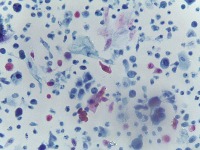

Medical Diagnostics: This model can be used in the healthcare industry to provide high-speed automated analysis of pathology slides, determining whether cells are normal or abnormal, and assisting in diagnosis of various diseases such as cancer.

Scientific Research: Researchers studying cell biology or genetics can use this AI model for their studies on cellular abnormalities and diseases. This can accelerate the onset of breakthroughs in medical science.

Pharmaceutical Applications: Pharmaceutical companies can use this model in drug discovery and development process. By identifying how different medications affect normal and abnormal cells, they can speed up and enhance their research.

Educational Tool: This AI model could serve as a rich educational tool in courses related to biology, medicine and health sciences, helping students to visualize and understand differences between normal and abnormal cells.

Personalized Medicine: This model can be used to analyze patients' cells to create personalized treatment plans. Understanding an individual's cellular structure could help healthcare professionals tailor treatments to the patient's specific needs.